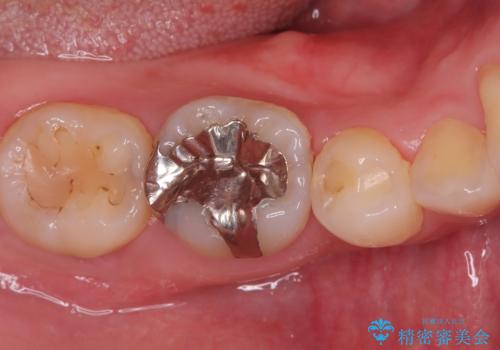

歯と歯の間の虫歯もセラミックで再発防止

担当医 河口智英